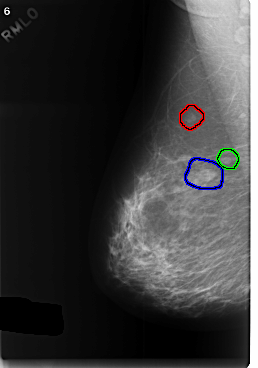

C_0374_1.RIGHT_MLO

RIGHT_MLO LINES 5880 PIXELS_PER_LINE 4120 BITS_PER_PIXEL 12 RESOLUTION 50 OVERLAY

FILE: C_0374_1.RIGHT_MLO.OVERLAY

TOTAL_ABNORMALITIES 3

ABNORMALITY 1

LESION_TYPE MASS SHAPE LOBULATED MARGINS CIRCUMSCRIBED

ASSESSMENT 3

SUBTLETY 5

PATHOLOGY BENIGN

ABNORMALITY 2

LESION_TYPE MASS SHAPE ROUND MARGINS CIRCUMSCRIBED

ABNORMALITY 3

LESION_TYPE MASS SHAPE LOBULATED MARGINS MICROLOBULATED